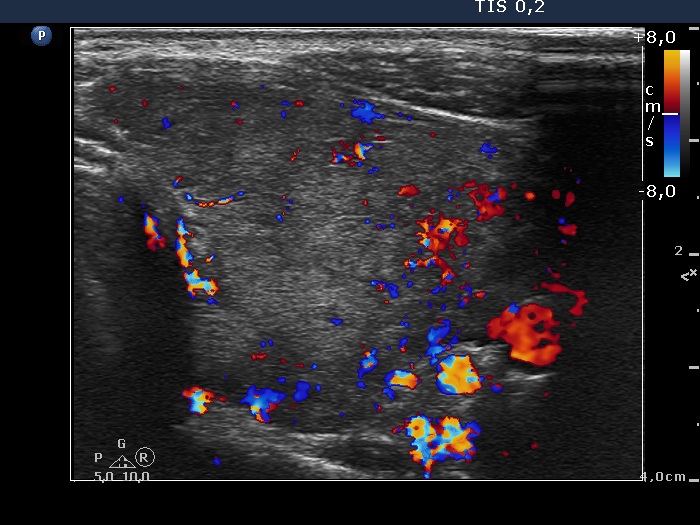

Left lobe, transverse scan, color Doppler mode. The vascularization is a bit increased.